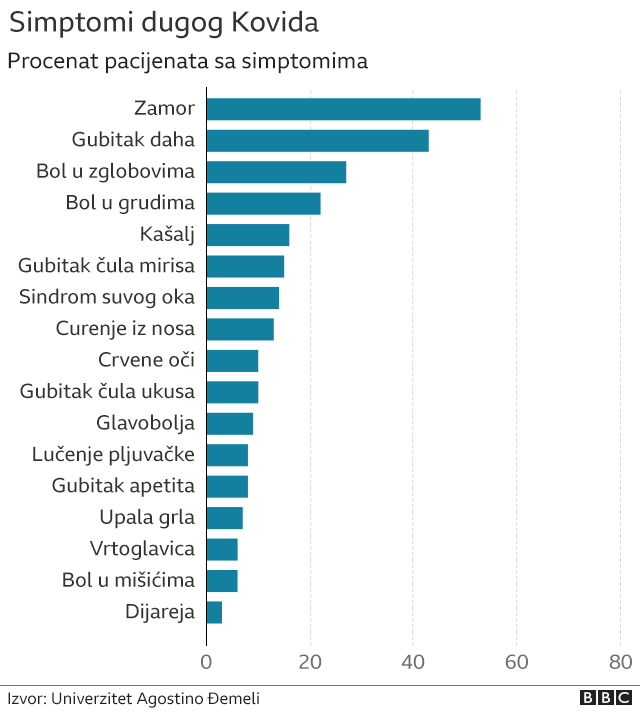

Ostali simptomi su ostajanje bez daha, kašalj koji ne prolazi, bolne zglobove, bol u mišićima, probleme sa vidom i sluhom, glavobolje, gubitak čula mirisa i ukusa, kao i oštećenje srca, pluća, bubrega i creva.

Prijavljeni su i problemi sa psihičkim zdravljem, kao što su depresija, anksioznost i nedostatak koncentracije.

Studija sprovedena na 143 osobe u najvećoj rimskoj bolnici, objavljena u Časopisu Američkog medicinskog udruženja, pratila je bolničke pacijente nakon što su otpušteni kućama.

Pokazalo se da je njih 87 odsto imalo najmanje jedan simptom skoro dva meseca kasnije, a više od polovine i dalje je osećalo umor.